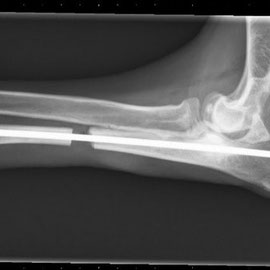

Der Tierschutzverein Iserlohn eV hat Ben als Welpen aus Polen übernommen, wo er in einer Tierstation lebte. Bens Vorderbeinchen war deformiert und er brauchte jetzt eine Operation, damit Ben schmerzfrei durchs Leben laufen kann. Ben ist gerade einmal 8 Monate alt und hat hoffentlich noch ein langes Leben vor sich, das er als gesunder Hund leben dürfen sollte! Die Kosten der Operation und der Nachbehandlungen werden wohl bei mehr als 800,-- € liegen....